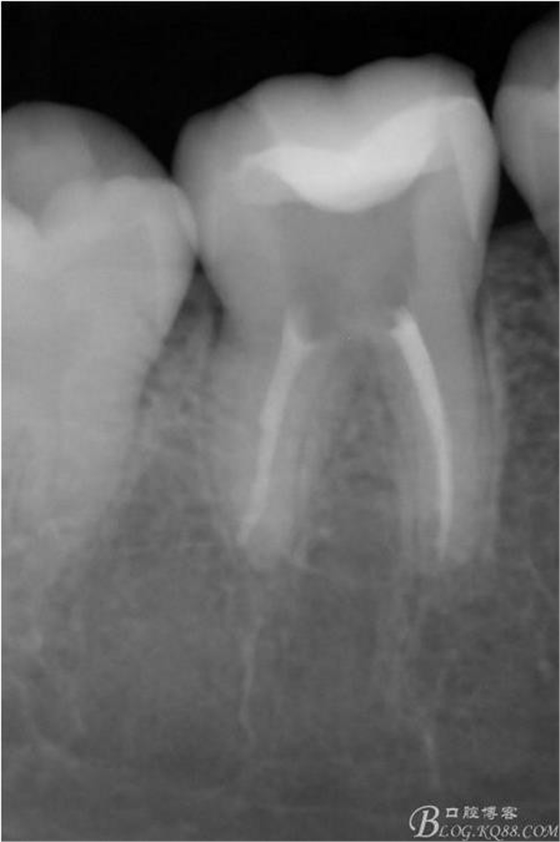

X線:雙側(cè)下6 齲壞已接近髓腔

診斷:雙側(cè)下6 慢性牙髓炎

治療方案:雙側(cè)RCT+CAD-CAM

粘接后X線片